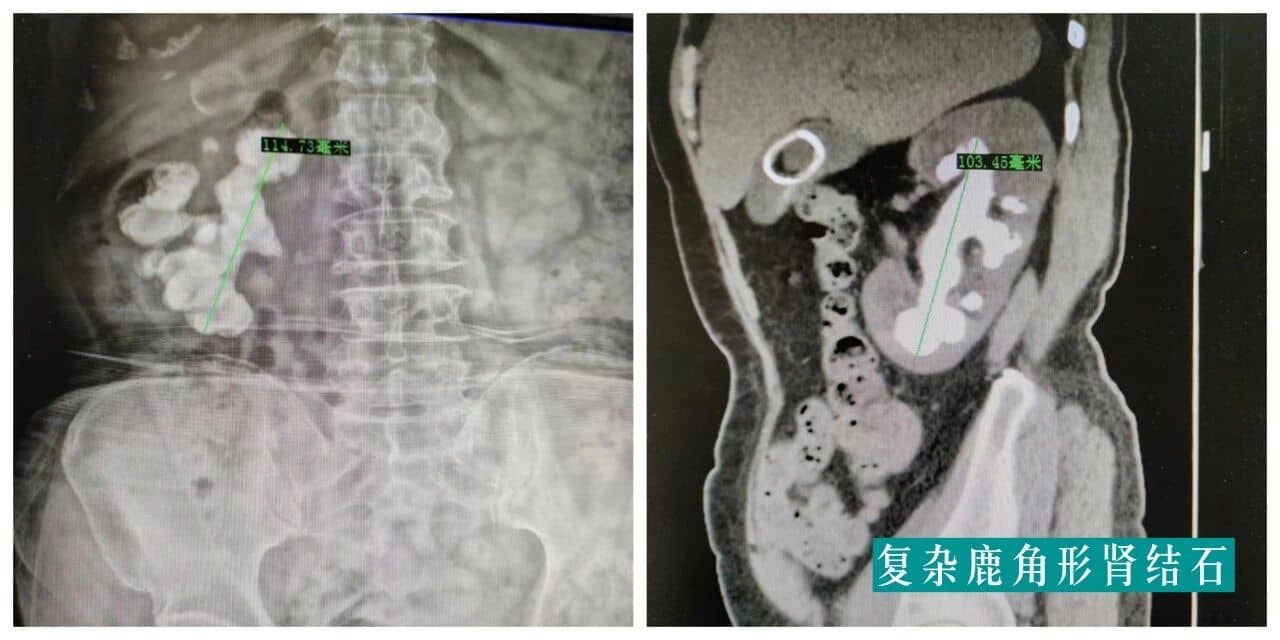

(二)复杂型泌尿系结石

科室结石治疗设备目前在莆田较齐全、先进,技术上也处于领先地位。能够熟练地开展体外震波碎石、开放切开取石、腹腔镜切开取石、经尿道膀胱镜/输尿管硬(软)镜碎石、经皮肾镜碎石等各种治疗技术,并发症少、成功率高,拥有上千例经皮肾镜碎石手术经验。对肾结石、输尿管结石、膀胱尿道结石的治疗,目前基本已采用各种微创/腔内技术治疗,疗效好、恢复快,多数在3-7天内出院。